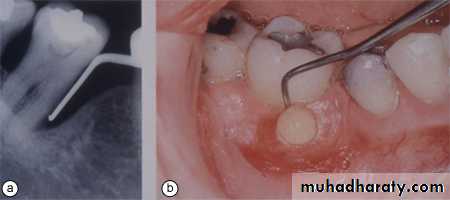

If it is possible to obtain a screening radiograph, such as an orthopantomograph (OPG), this may assist in the diagnosis and localisation of the cause of the pain. The radiograph should show clearly the apical and periapical structures of teeth and associated tissues. The relationship of the maxillary molars and premolars to the floor of the maxillary sinus can be examined, and radiographs may reveal recurrent caries or periapical radiolucencies associated with an established infection.

Radiographic examination